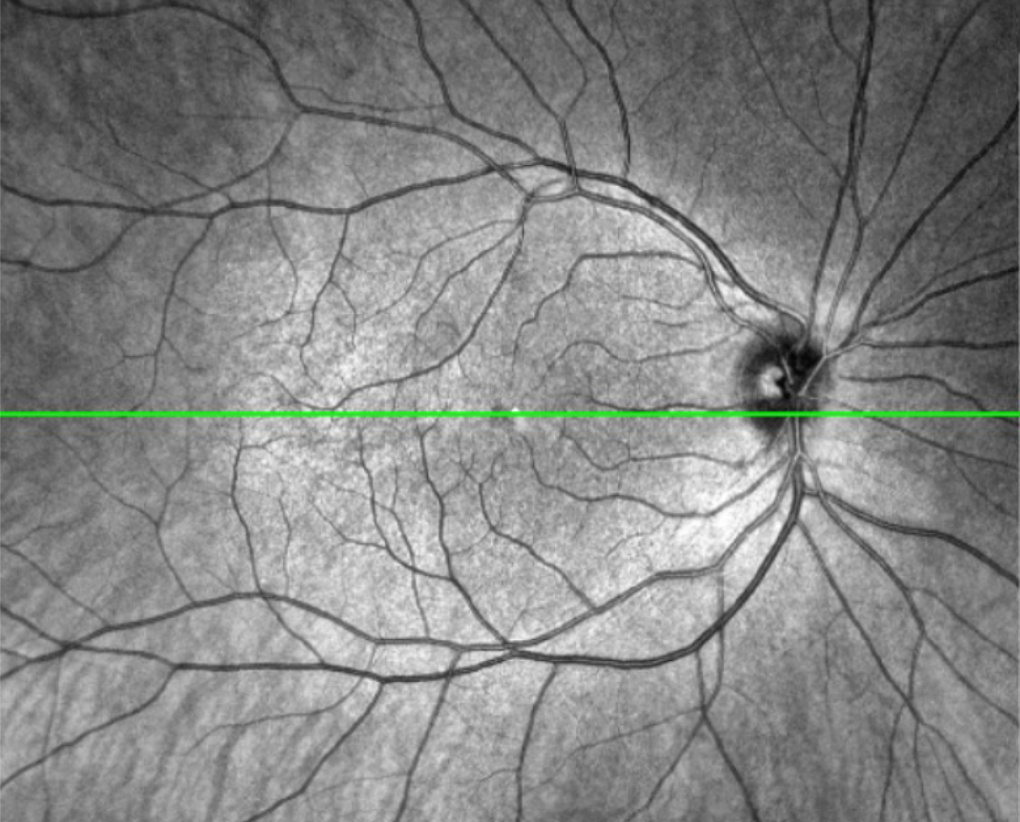

Bei einer OCT wird ein spezieller Scanner verwendet, der mithilfe von Lichtwellen die Netzhaut und andere Augenstrukturen in hoher Auflösung abbilden kann. Das Licht wird in das Auge gesendet, wo es von den verschiedenen Gewebeschichten reflektiert wird. Die reflektierten Lichtwellen werden dann vom Scanner erfasst und in ein digitales 3D-Bild (Tomografie) umgewandelt. Das akustische Pendant dazu ist die Sonographie.

- Netzhauterkrankungen: Die OCT kann Veränderungen in den verschiedenen Schichten der Netzhaut identifizieren, was bei der Diagnose von Erkrankungen wie Makuladegeneration und diabetischer Retinopathie hilfreich ist.

- Grüner Star: Durch die Beurteilung des Zustands des Sehnervs und der retinalen Nervenfaserschicht kann die OCT helfen, das Glaukom frühzeitig zu erkennen und den Verlauf der Erkrankung zu überwachen.